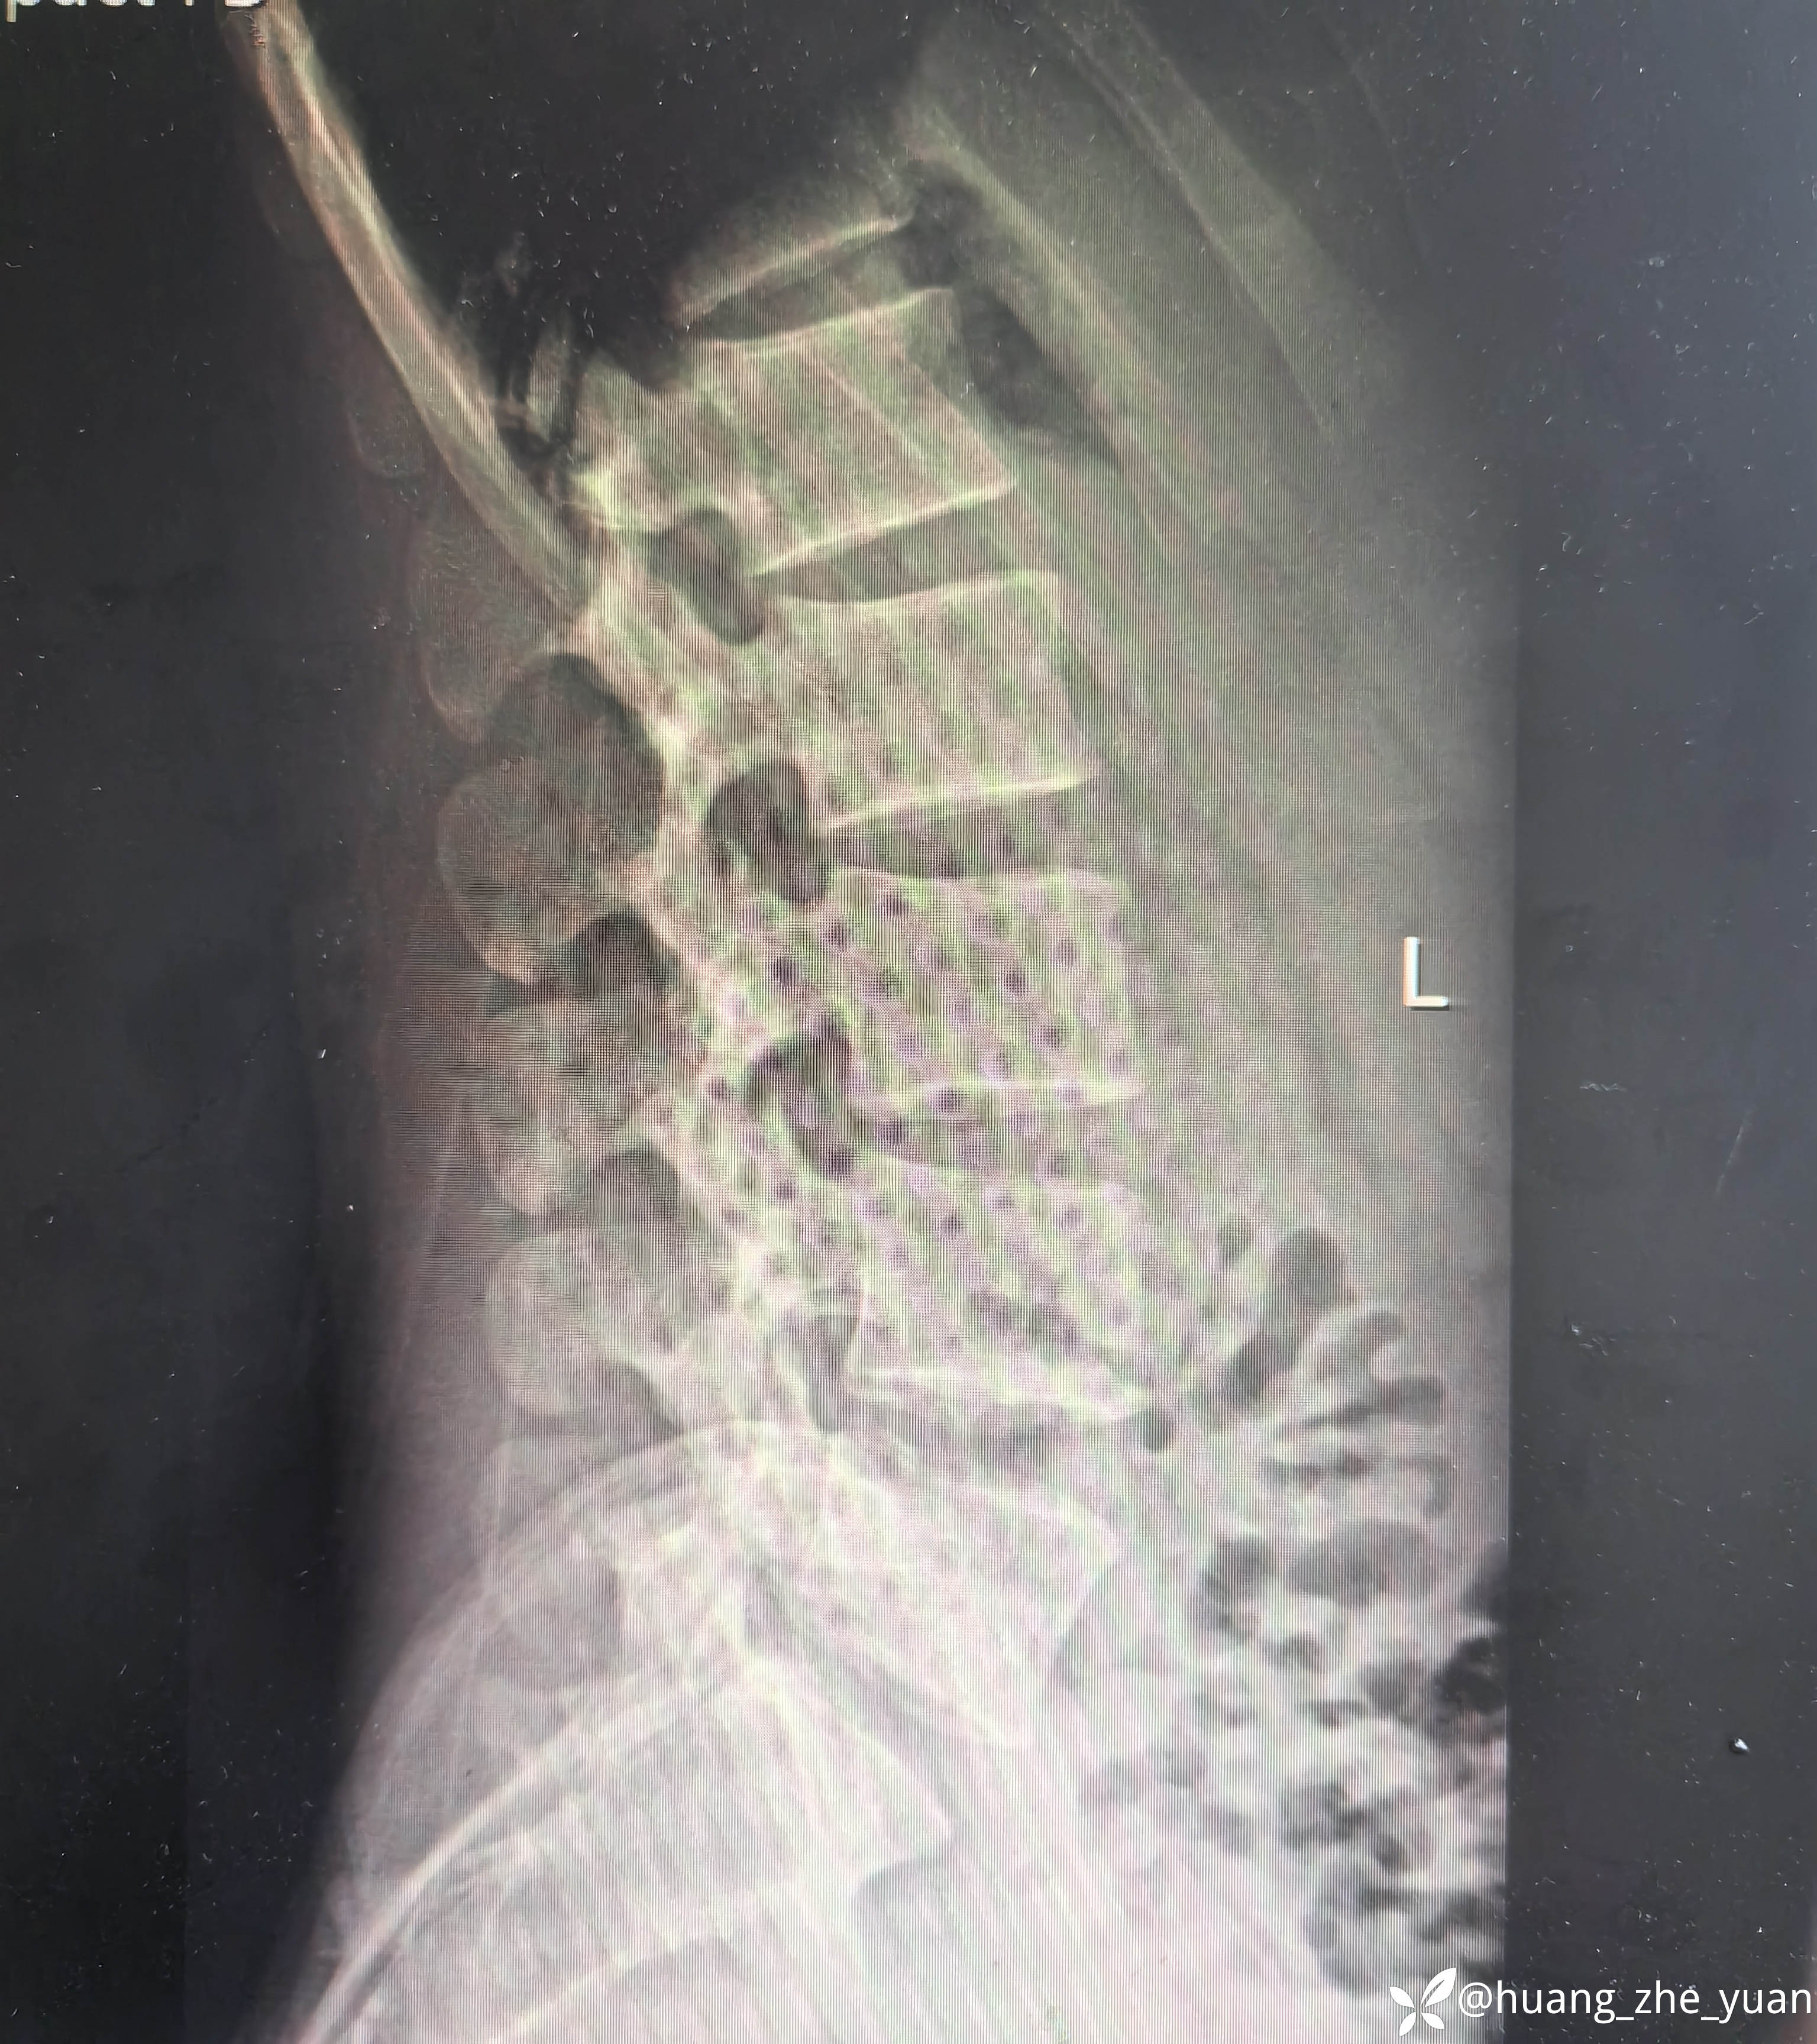

病人20岁,非常年轻,但是腰痛症状很明显,全天24小时无缓解,术前腰痛VAS评分7分,腿几乎不痛。保守治疗无效,融合又太早,和病人沟通后建议内镜下射频消融,术中尽量减少创伤。